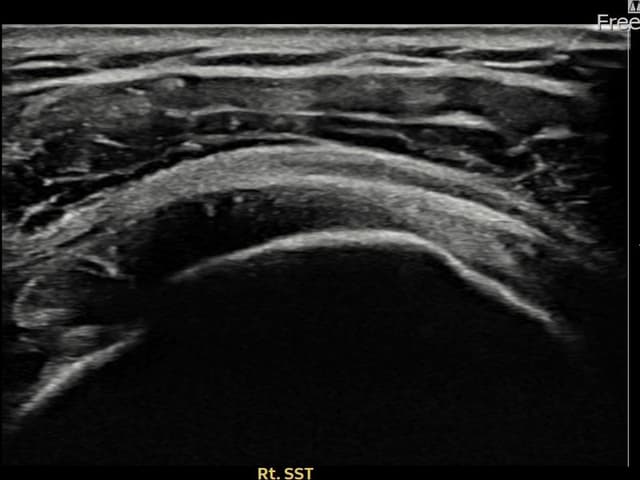

[촬영시기:23.09.19~23.11.21]

[어깨인대 축소봉합술] 우측 어깨 통증과 야간 통증으로 수면 장애가 있어 내원하셨습니다.